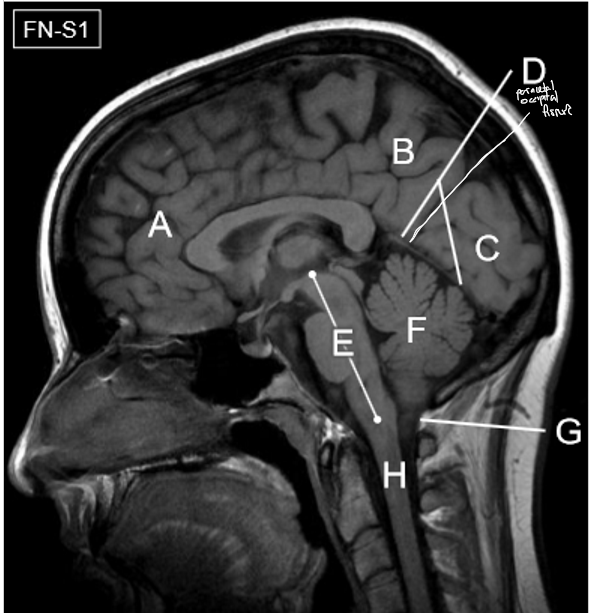

D-H

D: Tentorium cerebelli

E: Brainstem

F: Cerebellum

G: Foramen magnum

H: Spinal cord

A-D

A: Superior sagittal sinus

B: Inferior sagittal sinus

C: Straight sinus

D: Confluence of sinuses